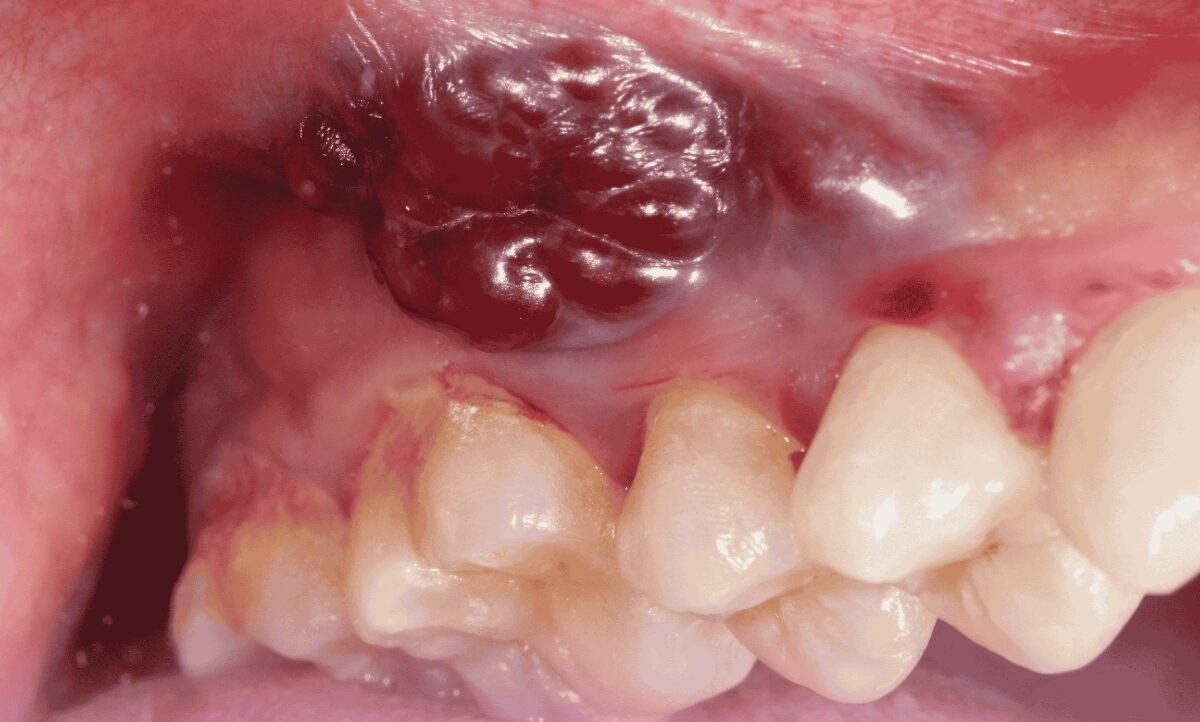

Oral (Mouth) cancer arises when malignant cells develop in or around the mouth, affecting areas like the lips, tongue, gums, cheeks, and the upper or lower jaw. This condition can disrupt normal speech patterns by altering the movements or size of various parts of the mouth. Additionally, it can lead to difficulties in chewing and swallowing.

Oral cancer refers to the abnormal growth of cells in the mouth or oral cavity. It can affect various areas, including the lips, tongue, cheek lining, gums, and floor of the mouth. If left untreated, oral cancer can spread to other parts of the body, leading to severe health complications. Airavat Cancer Care is provide best oral cancer doctor in Ahmedabad.

Oral cancer can be caused by multiple factors, including tobacco use, excessive alcohol consumption, human papillomavirus (HPV) infection, and prolonged sun exposure. Early symptoms of oral cancer may include persistent mouth sores, pain or difficulty while swallowing, a lump or thickening in the cheek, and unexplained bleeding in the mouth. If you notice any of these symptoms, it is crucial to consult a healthcare professional for a thorough evaluation and diagnosis. Airavat Cancer Care is the most trusted hospital for larynx cancer & maxillary cancer treatment in Ahmedabad.

Oral cancer has several signs and symptoms that may be mistaken for common problems or changes in your mouth. For example, you may notice patches inside of your mouth that you can’t scrape away. These patches may be pre-cancerous conditions.